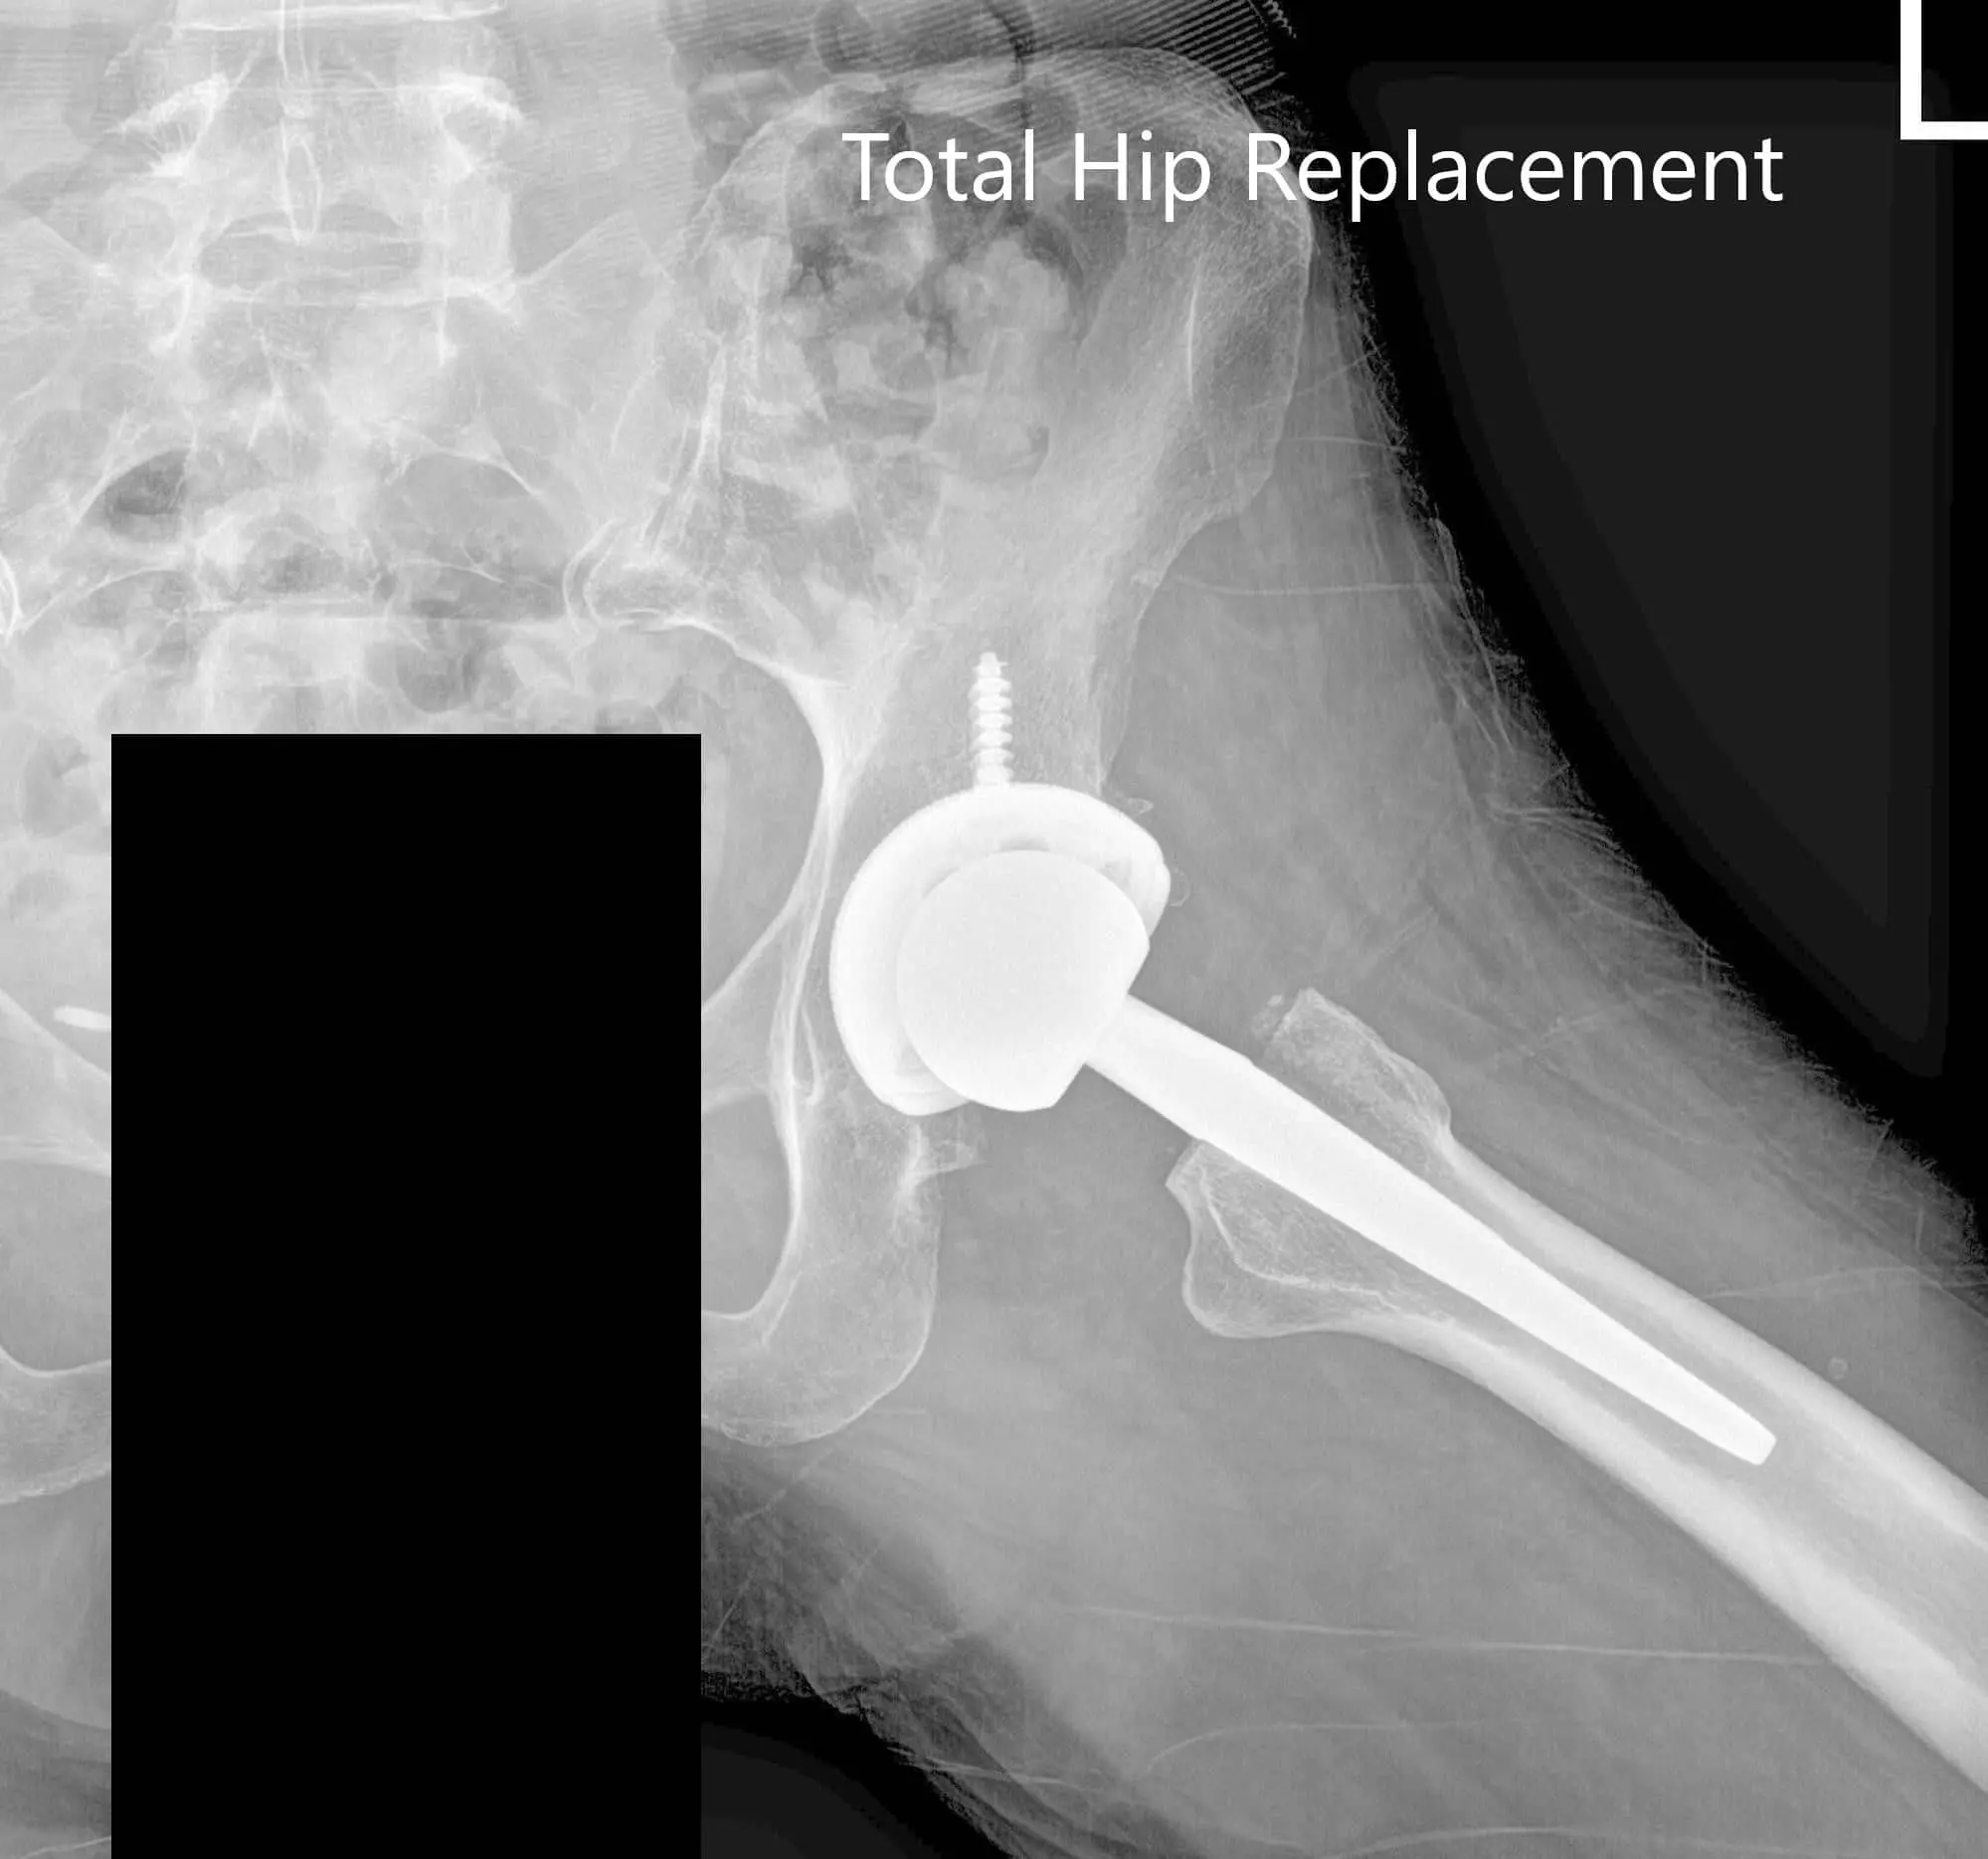

The patient returned for a total hip replacement of the left side two months later. He was enthusiastic about the success of the right hip arthroplasty. He underwent a left total hip replacement with an acetabular shell of 52 mm and a 0-degree polyethylene insert. Additionally, a 6.5 mm x 25 mm cancellous screw was used for fixation. A ceramic head of 36 mm was used with a127 degree angle hip stem (stem length – 102 mm and neck length -30 mm).

Postoperative X-ray of the left hip showing AP and lateral views.